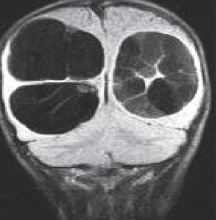

(Слева) Т1 -ВИ, сагиттальная проекция, FS+КУ: не накапливающее контраст экстрадуральное кистозное образование в области КВС, являющееся причиной компрессии соседнего участка спинного мозга. Обратите также внимание на имеющиеся признаки врожденной аномалии КВС.

(Справа) Это аксиальное Т2-ВИ подтверждает диагноз нейроэнтеральной кисты, выполняющей задне-боковой отдел спинномозгового канала и смещающей шейный отдел спинного мозга ЕЕ вперед и влево.

(Слева) Т1-ВИ, сагиттальная проекция (синдром Клиппеля-Фейля): небольшая вентральная интрадуральная экстрамедуллярная нейроэнтеральная киста, сдавливающая вентральную часть спинного мозга. Также на этом изображении видна зубовидная кость.

(Справа) На аксиальном Т2-ВИ у пациента с синдромом Клиппеля-Фейля выявлена небольшая гиперинтенсивная экстрамедуллярная нейроэнтеральная киста, деформирующая и смещающая кзади шейный отдел спинного мозга.

(Слева) На сагиттальном КТ-срезе после введения контраста определяется вентральное интрадуральное объемное образование В на уровне СЗ-С4, умеренно сдавливающее спинной мозг.

(Справа) На аксиальном КТ-срезе после интратекального введения контраста определяется вентральное интрадуральное объемное образование, представляющее собой нейроэнтеральную кисту. Признаков аномалий сегментации позвонков не видно.